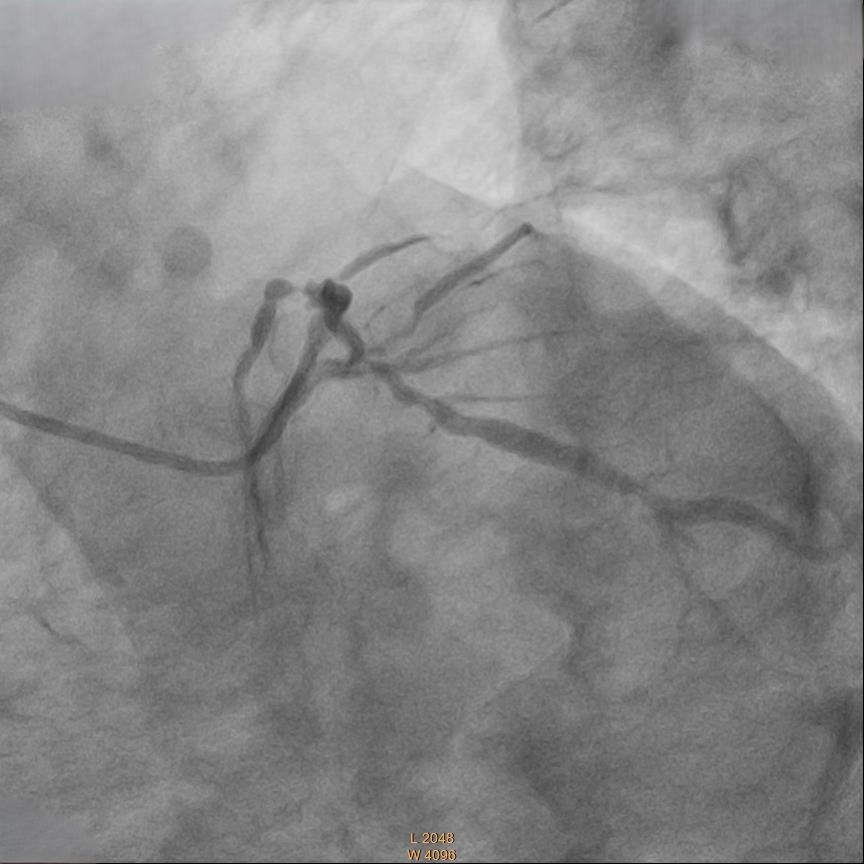

Right femoral artery punctured approach by 7Fr femoral sheath. Coronary guide catheter EBU 3.5 was used to engage left coronary artery. Percutaneous Coronary Intervention (PCI) to bifurcation Medina 1,1,1 using T and small protrusion (TAP) technique. LAD and LCX wired with workhorse wire . Mid LAD predilated with Semi-compliant (SC)2.5mm balloon and proximal LAD predilated with non-compliance (NC) 3.5mmballoon. Intravascular Ultrasound ( IVUS) was performed to measure the vessel size, lesion length and plaque morphology. Mid LAD stented with 3.5x23 mm drug eluting stent (DES). LM until proximal LAD stented with 4x33mm DES . Proximal optimization therapy (POT) at LM with NC balloon 5x8mm. Proximal LAD post dilated with NC balloon 4x20mm and mid LAD post dilated with NC balloon 3.5x15mm. LCX rewired with workhorse wire. Ostial LCX predilated with NC balloon 3.5x15mm and stented with 3.5x23mm DES subsequently post dilated with NC balloon 3.75x20mm. Final kissing balloon inflation was done at ostial LAD using NC balloon 4.0 and ostial LCX using NC balloon 3.75. Final IVUS noted double barrel sign at LM stent and confirmed with stent enhancement likely due to abluminal side branch wiring. Final POT to LM with NC balloon 5x8mm. Final IVUS showed good stent expansion and opposition with no dissection.

Case Summary

This case highlighted the importance of using IVUS in doing PCI. Importance of intravascular imaging in PCI was highlighted in recent 2024ESC guidelines and it’s class 1 evidence. Besides assessing the lesion length, diameter and plaque morphology, it can ensure good stent opposition and expansion. This is crucial to prevent complication during bifurcation stenting.